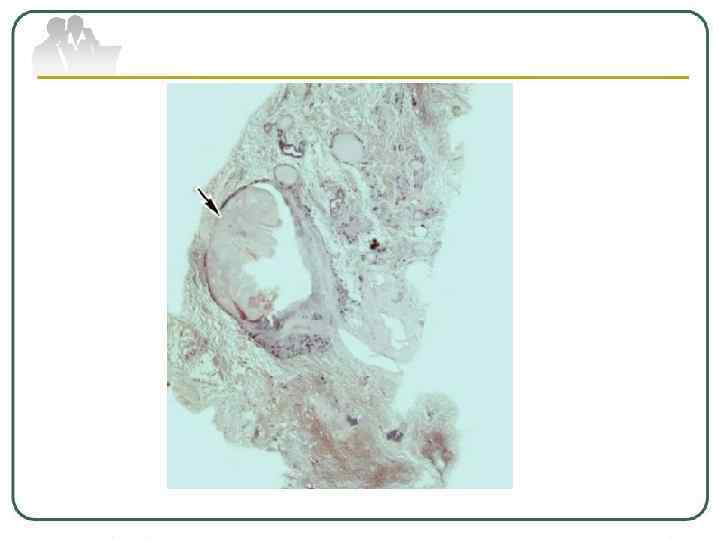

Туберкулема легких - понятие, объединяющее разнообразные по генезу инкапсулированные казеозные фокусы величиной более 1, 0 см в диаметре. Различают туберкулемы иифильтративно-пневмонического типа, гомогенные, слоистые, конгломератные и так называемые "псевдотуберкулемы" - заполненные каверны. На рентгенограмме туберкулемы выявляются в виде тени округлой формы с четкими контурами. В фокусе может определяться серповидное просветление за счет распада, иногда перифокальное воспаление и небольшое количество бронхогенных очагов, а также участки обызвествления.